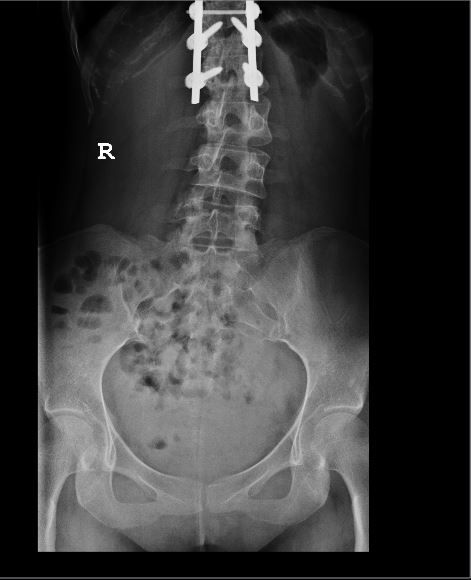

This is the implant inside my body. My spine was originally a ‘S’ shape spine.

It is not entirely straight now as you can see from the Xray..